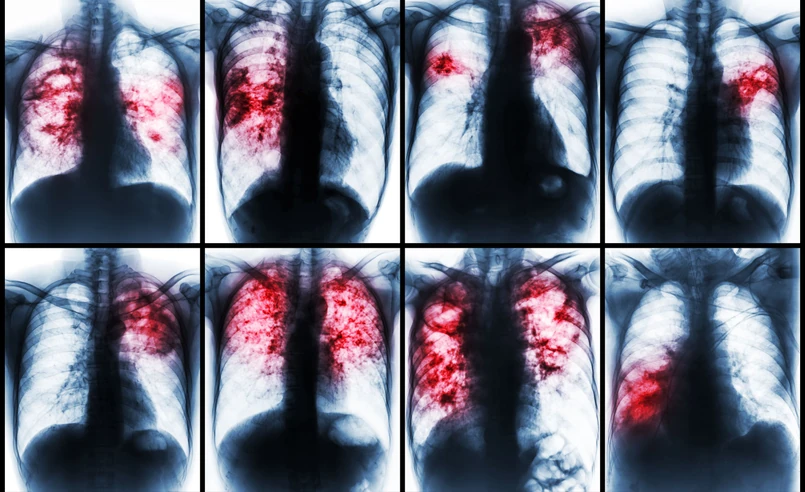

Gruźlica na zdjęciu rentgenowskim

<p>Gruźlica na zdjęciu rentgenowskim</p>/Shutterstock